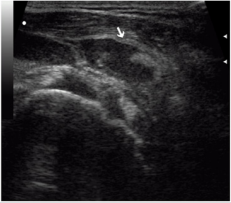

A complete rupture of the rotator cuff against the background of acute in-jury occurred in 64.8% of cases, against the background of chronic injury - in 35.2% of cases, respectively (P <0.05). The absence of tendon imaging in a typical place was detected in 70% of cases, while in the sonogram the humeral head contour was determined (70%) with adjoining the deltoid muscle (70%). Such an echographic picture corresponded to a massive rupture of a rotator cuff with damage to several tendons. In 96% of cases, complete rupture of the rotator cuff of the shoulder was accompanied by effusion in the subdeltoid-subacromial bag, in 90% of cases the effusion had a heterogeneous structure with hyperechoic inclusions, indicating the organization of the hematoma. In 57% of cases with identified effusion in the wall of the sub-deltoid-subacromial bag there was an increase in vascularization (Figures 1-4).

Figure 2: Echogram of complete rupture of the rotator cuff. Intermittent rotator cuff with a diasta-sis of broken tendon ends. The fistula with subdeltoid-subacromial bag is visualized (arrows).